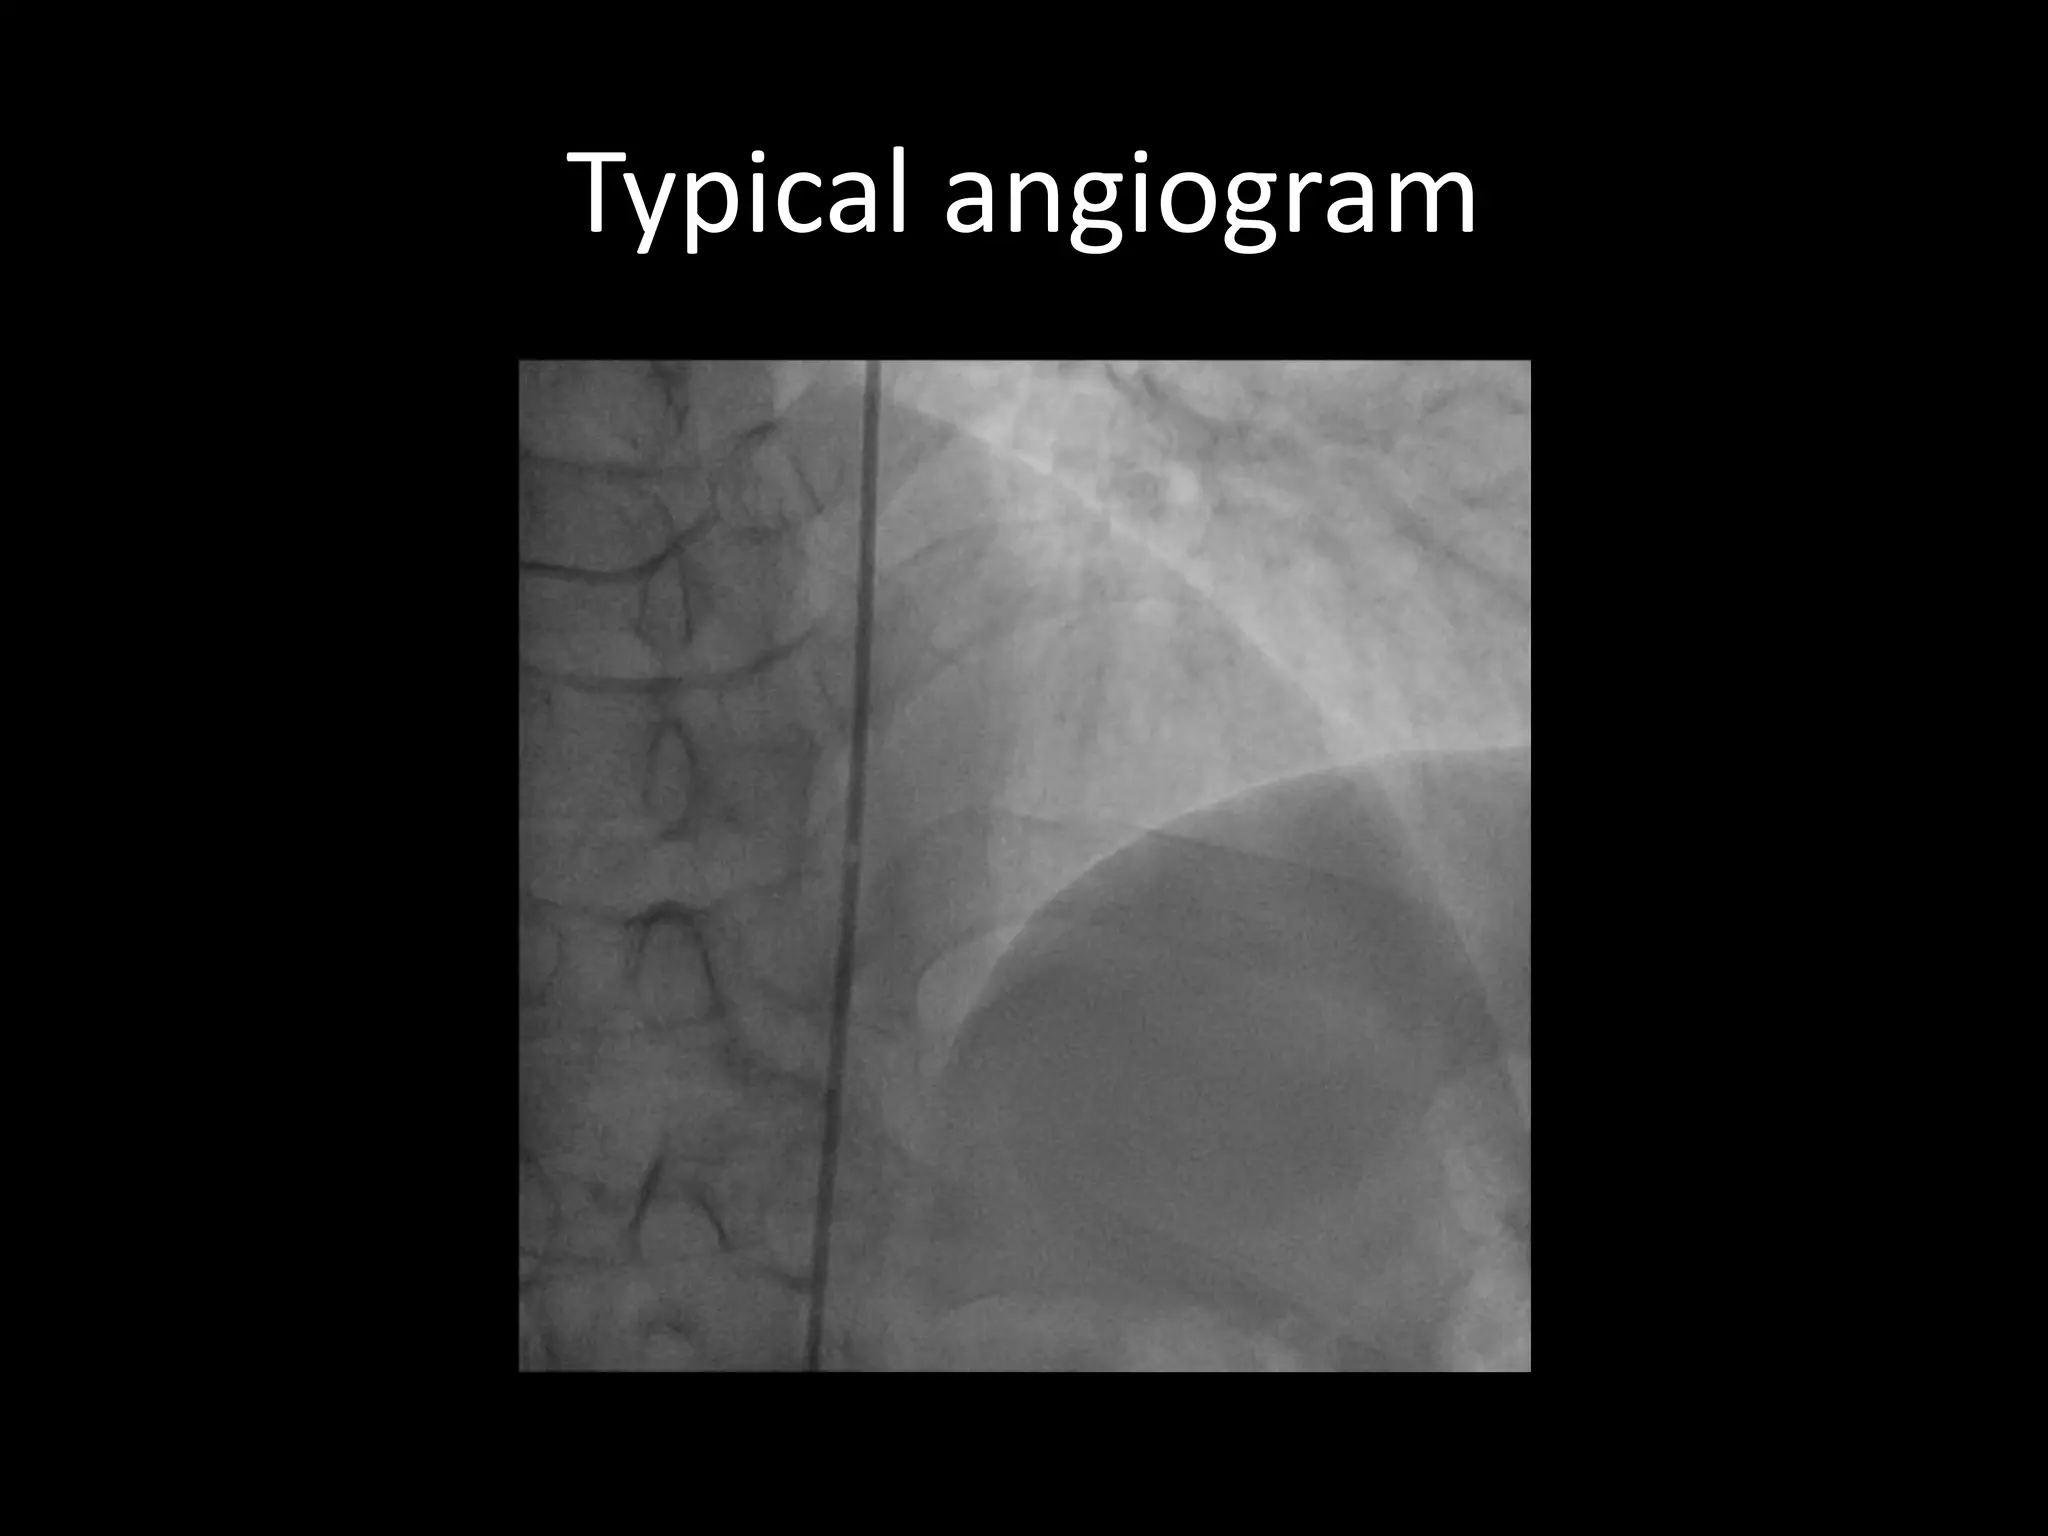

This document provides guidance on evaluating the feasibility of percutaneous coronary intervention (PCI) for a chronic total occlusion (CTO). Key factors to consider include: the patient's tolerance for a long procedure, contrast load, and radiation exposure; the CTO's proximal cap ambiguity, length, distal landing zone, and presence of interventional collaterals; and ensuring good quality angiography. With adequate planning and use of appropriate CTO techniques, feasibility is nearly always present for symptomatic patients. Success rates of CTO-PCI are reported to be 94% when using a planned approach.